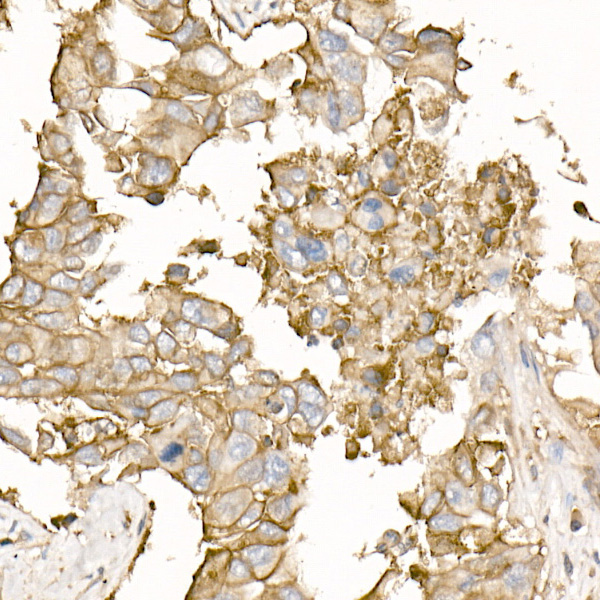

Immunohistochemistry of paraffin-embedded human liver cancer using Na+/K+-ATPase Rabbit pAb.

Immunohistochemistry of paraffin-embedded human lung cancer using Na+/K+-ATPase Rabbit pAb.

Immunohistochemistry of paraffin-embedded mouse kidney using Na+/K+-ATPase Rabbit pAb.